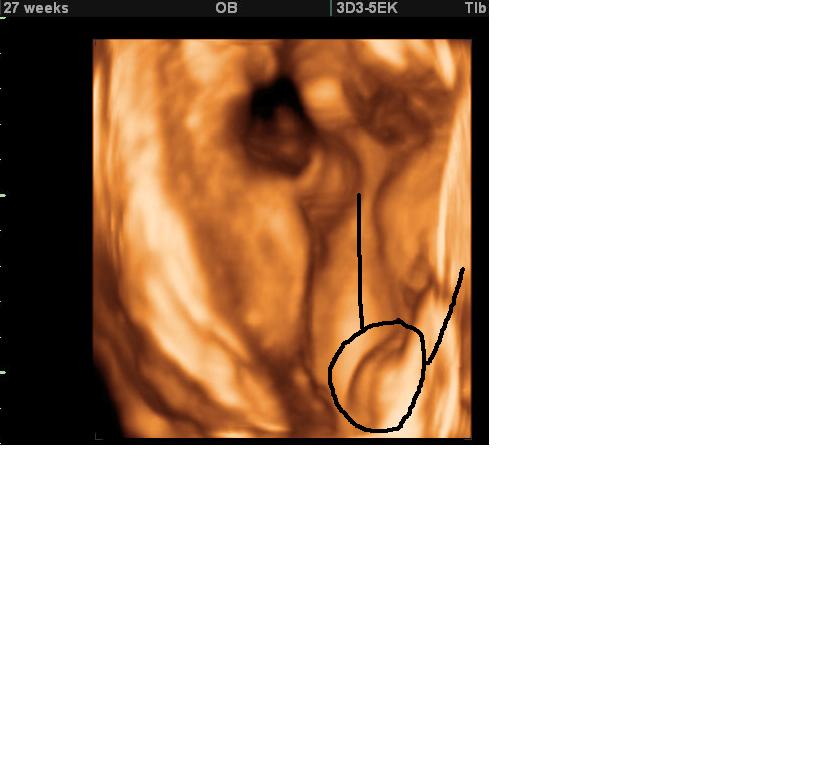

Here are the 3d scan pics of my daughter at 27 weeks, i have made a circle around her VJ and the lines are her legs.